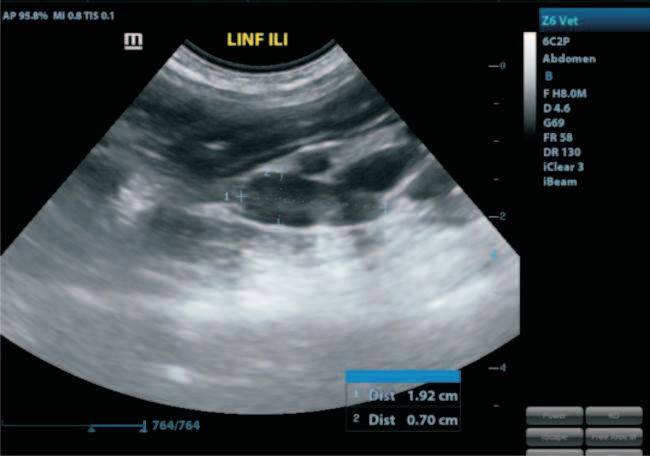

La ecografía transabdominal permite observar estas estructuras como cavidades bien definidas, anecoicas, de pared delgadaycontenidolíquido.Noobstante, el hallazgo más común se produce de forma incidental durante procedimientos quirúrgicoscomolaOSH,enpacientescarentesdealteracionesclínicasevidentes.10 Estos hallazgos deben ser abordados con criterios diagnósticos claros, ya que otros tipos de quistes o incluso ciertas neoplasiasováricaspuedentenerpresentaciones macroscópicas similares.11

Lo anterior se refuerza en los casos reportados, por Szczepanik, et al.,12 quienes describieron la presencia de quistes foliculares múltiples en una paciente, sin evidencia de signos clínicos.